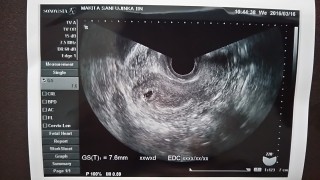

2016.3.16。 本日、人生で初めての妊娠の診断。 まだ実感はありませんが、 「この左上の黒い空洞の様なところが胎嚢ですよ」と言われました。 次は約二週間後です、心拍出てるかなー

排卵検査もしていたので、計算に間違いがなければ5w3dです。 ピンクのおりものや少量の鮮血もみられていたので心配で、もう少し後の受診を予定していましたが、この日に受診してきました。 前回は5wでも確認が出来ず6w後半で流産しているのですごく不安だったんですが、前回より早い段階でしかも前より良い感じの胎嚢を確認出来ました! 赤ちゃんの素となるものも確認出来たとのことです。まんまる卵。 次回は3週間後。長いし不安ですが赤ちゃん信じて過ごします!